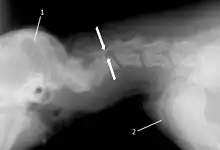

The disease tends to be gradually progressive. Symptoms such as weakness, ataxia, and dragging of the toes start in the rear legs. Dogs often have a crouching stance with a downward flexed neck. The disease progresses to the front legs, but the symptoms are less severe. Neck pain is sometimes seen. Symptoms are usually gradual in onset, but may progress rapidly following trauma.[6] X-rays may show misaligned vertebrae and narrow disk spaces, but it is not as effective as a myelogram, which reveals stenosis of the vertebral canal. Magnetic resonance imaging has been shown to be more effective at showing the location, nature, and severity of spinal cord compression than a myelogram.[7] Treatment is either medical to control the symptoms, usually with corticosteroids and cage rest, or surgical to correct the spinal cord compression. The prognosis is guarded in either case. Surgery may fully correct the problem, but it is technically difficult and relapses may occur. Types of surgery include ventral decompression of the spinal cord (ventral slot technique), dorsal decompression, and vertebral stabilization.[8] One study showed no significant advantage to any of the common spinal cord decompression procedures.[9] Another study showed that electroacupuncture may be a successful treatment for Wobbler disease.[10] A new surgical treatment using a proprietary medical device has been developed for dogs with disc-associated wobbler disease. It implants an artificial disc (cervical arthroplasty) in place of the affected disc space.[11]

Wobbler disease is definitively diagnosed by x-ray, nuclear scintigraphy or bone scan. X-rays will show channel widening or filling the easiest and are often most cost-effective to horse owners. X-rays will also show any structural anomaly, arthritis, facet remodeling, or bone spurs present. Preliminary diagnosis can be made by ultrasound but x-rays are needed to measure the true depth of facet involvement. For extent of damage to associated structures, veterinarians may opt to have the horse undergo a bone scan or nuclear scintigraphy.